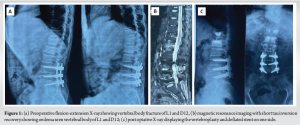

An elderly male presented with OVF of the L1 (with a bone mineral density showing a T-score of −3.7) of 3 weeks history with a pain in the back and intact neurology. The pain was severe with a visual analog score (VAS) scale 7/10 that was mechanical in nature aggravated with tuning on bed and on loading of spine. The X-ray showed a fracture of D12 and L1 (Fig. 1a) and it was confirmed on the magnetic resonance imaging (MRI) showing an acute fracture (Fig. 1b). He was planned for stentoplasty (VBS System, DePuy Synthes, Johnson & Johnson) at L1 and vertebroplasty at D12. The patient was positioned prone and given me an erector spine block at D11 level for the case. The field was sterilised and draped. A wide trocar (number 7) was railroaded over the guide wire pins. The guide wires were removed, a drill was passed in the trocar (Fig. 2a), and an impactor was placed to create the void (Fig. 2b). Nest, balloon was inserted inside and inflated (Fig. 2c), but beyond 22–25 atm (atmospheric pressure), the device was turning “false” and returned to zero. It happened on both sides and on both devices. The balloon was tested outside and found to be working adequately. The stent-mounted balloon was next inserted (Fig. 2d), and after a partial inflation on the left side, the stents did not expand. The right-side stent and balloon could not be inflated. The cement inserter failed to pass through the trocar; vertebroplasty was done on either side of the stent and also on the right side (Fig. 2e-f). At the proximal D12 level, vertebroplasty was done (Fig. 2g-h). Post-procedure, the neurology of the patient was intact. The post operative x-ray was satisfactory (Fig. 1c) and patient discharged next day after mobilisation. He had tremendous relief of pain (VAS of 1/10).